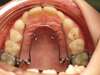

Avant expansion

Quadhélix en place : invisible